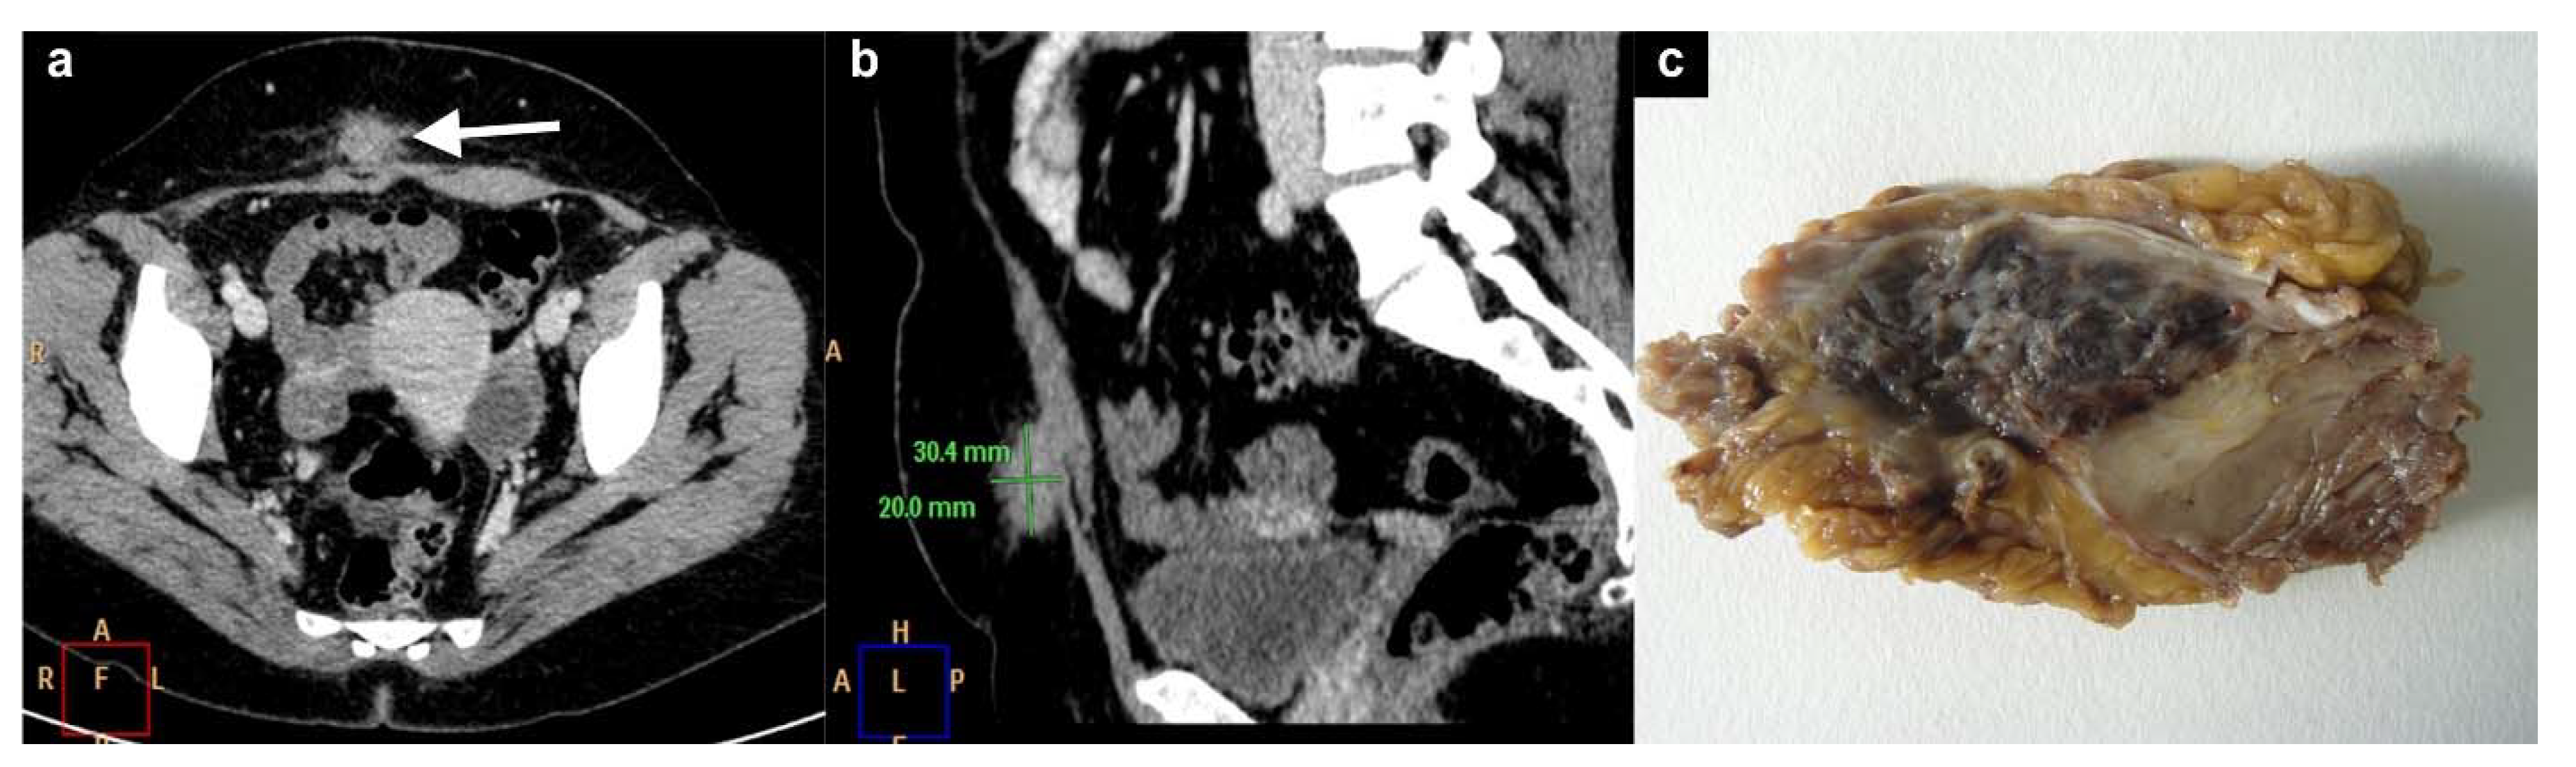

4. Subcutaneous Endometriosis